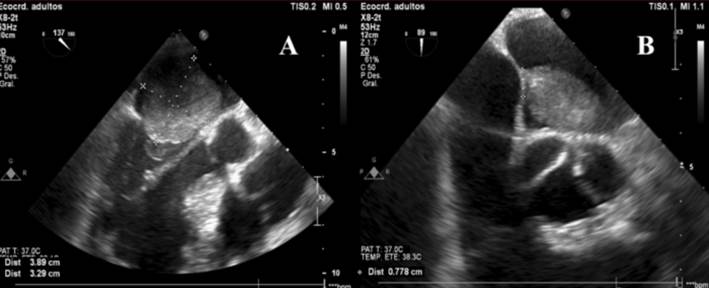

En dicho contexto es valorado por el equipo de cirugía cardíaca y se realiza resección quirúrgica urgente del mixoma con colocación de parche pericárdico a nivel auricular. El ecocardiograma transesofágico intraoperatorio (figura 3) constata la presencia del mixoma auricular y posteriormente confirma el buen resultado quirúrgico, habiéndose logrado extirpar la masa de forma satisfactoria (figura 4). En la evolución se solicitó Holter de 24 horas que informaba un registro ECG incambiado respecto al basal, sin evidencia de bloqueo AV de alto grado o completo. El paciente presentó buena evolución, se mantuvo estable hasta el momento del alta, sin reiterar episodios sincopales ni otra sintomatología de la esfera CV. Se otorgó el alta a domicilio luego de 7 días de posoperatorio.

Ecocardiograma transesofágico intraoperatorio. A) Proyección en eje largo esofágico medio a 137º. Se evidencia una gran masa de 39 x 33 mm, redondeada, de bordes irregulares, a nivel de la aurícula izquierda, que protruye al ventrículo izquierdo en diástole a través de la válvula mitral. B) Proyección en eje corto esofágico medio-superior a 89º. Se evidencia la masa intracardíaca ya mencionada, identificando claramente su pedículo con base de implantación de 8 mm de longitud en el septum interauricular. Las características descritas son compatibles con mixoma auricular.